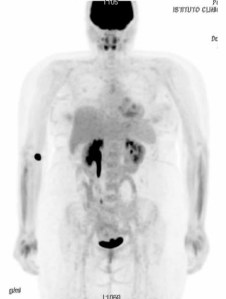

Immagini della PET assolutamente perfette.

Quello stesso pomeriggio è arrivato il referto della PET. Risultato negativo. L’esame è quindi risultato essere perfetto. Non c’era niente. Mi sono sentita morire. E’ difficile spiegare una sensazione del genere a persone che non hanno mai provato l’angoscia della malattia. Persino io che sono malata da quattordici anni provo sgomento per la reazione che ho avuto. L’esame era negativo, perché non potevo semplicemente esserne felice? La risposta è ovvia: perché sto male. Vorrei poter essere grata per il fatto che non ho tumore visibile ed ingombrante come ce l’avevo due anni fa, ma la verità è che per me quella sarebbe stata una strada facile. La più dura, senz’altro, ma indubbiamente la più semplice da seguire. Il motivo del mio dolore sarebbe stato evidente nell’esame e la strada da percorrere sarebbe stata chiara: chemio, auto-trapianto e magari un trapianto. Sarebbe stato straziante affrontare un percorso del genere ma avrei potuto indossare la mia armatura e combattere a muso duro, senza esclusione di colpi e senza sprecare tempo. Così, invece, tutto è più difficile. Davanti a me si prospettano mesi di ricoveri, di esami, di dolore. Sto male da quattordici anni, il dolore lo sopporto. Ma non lo voglio più provare. Sono esausta, voglio stare bene. Lo voglio disperatamente e con tutta l’anima.